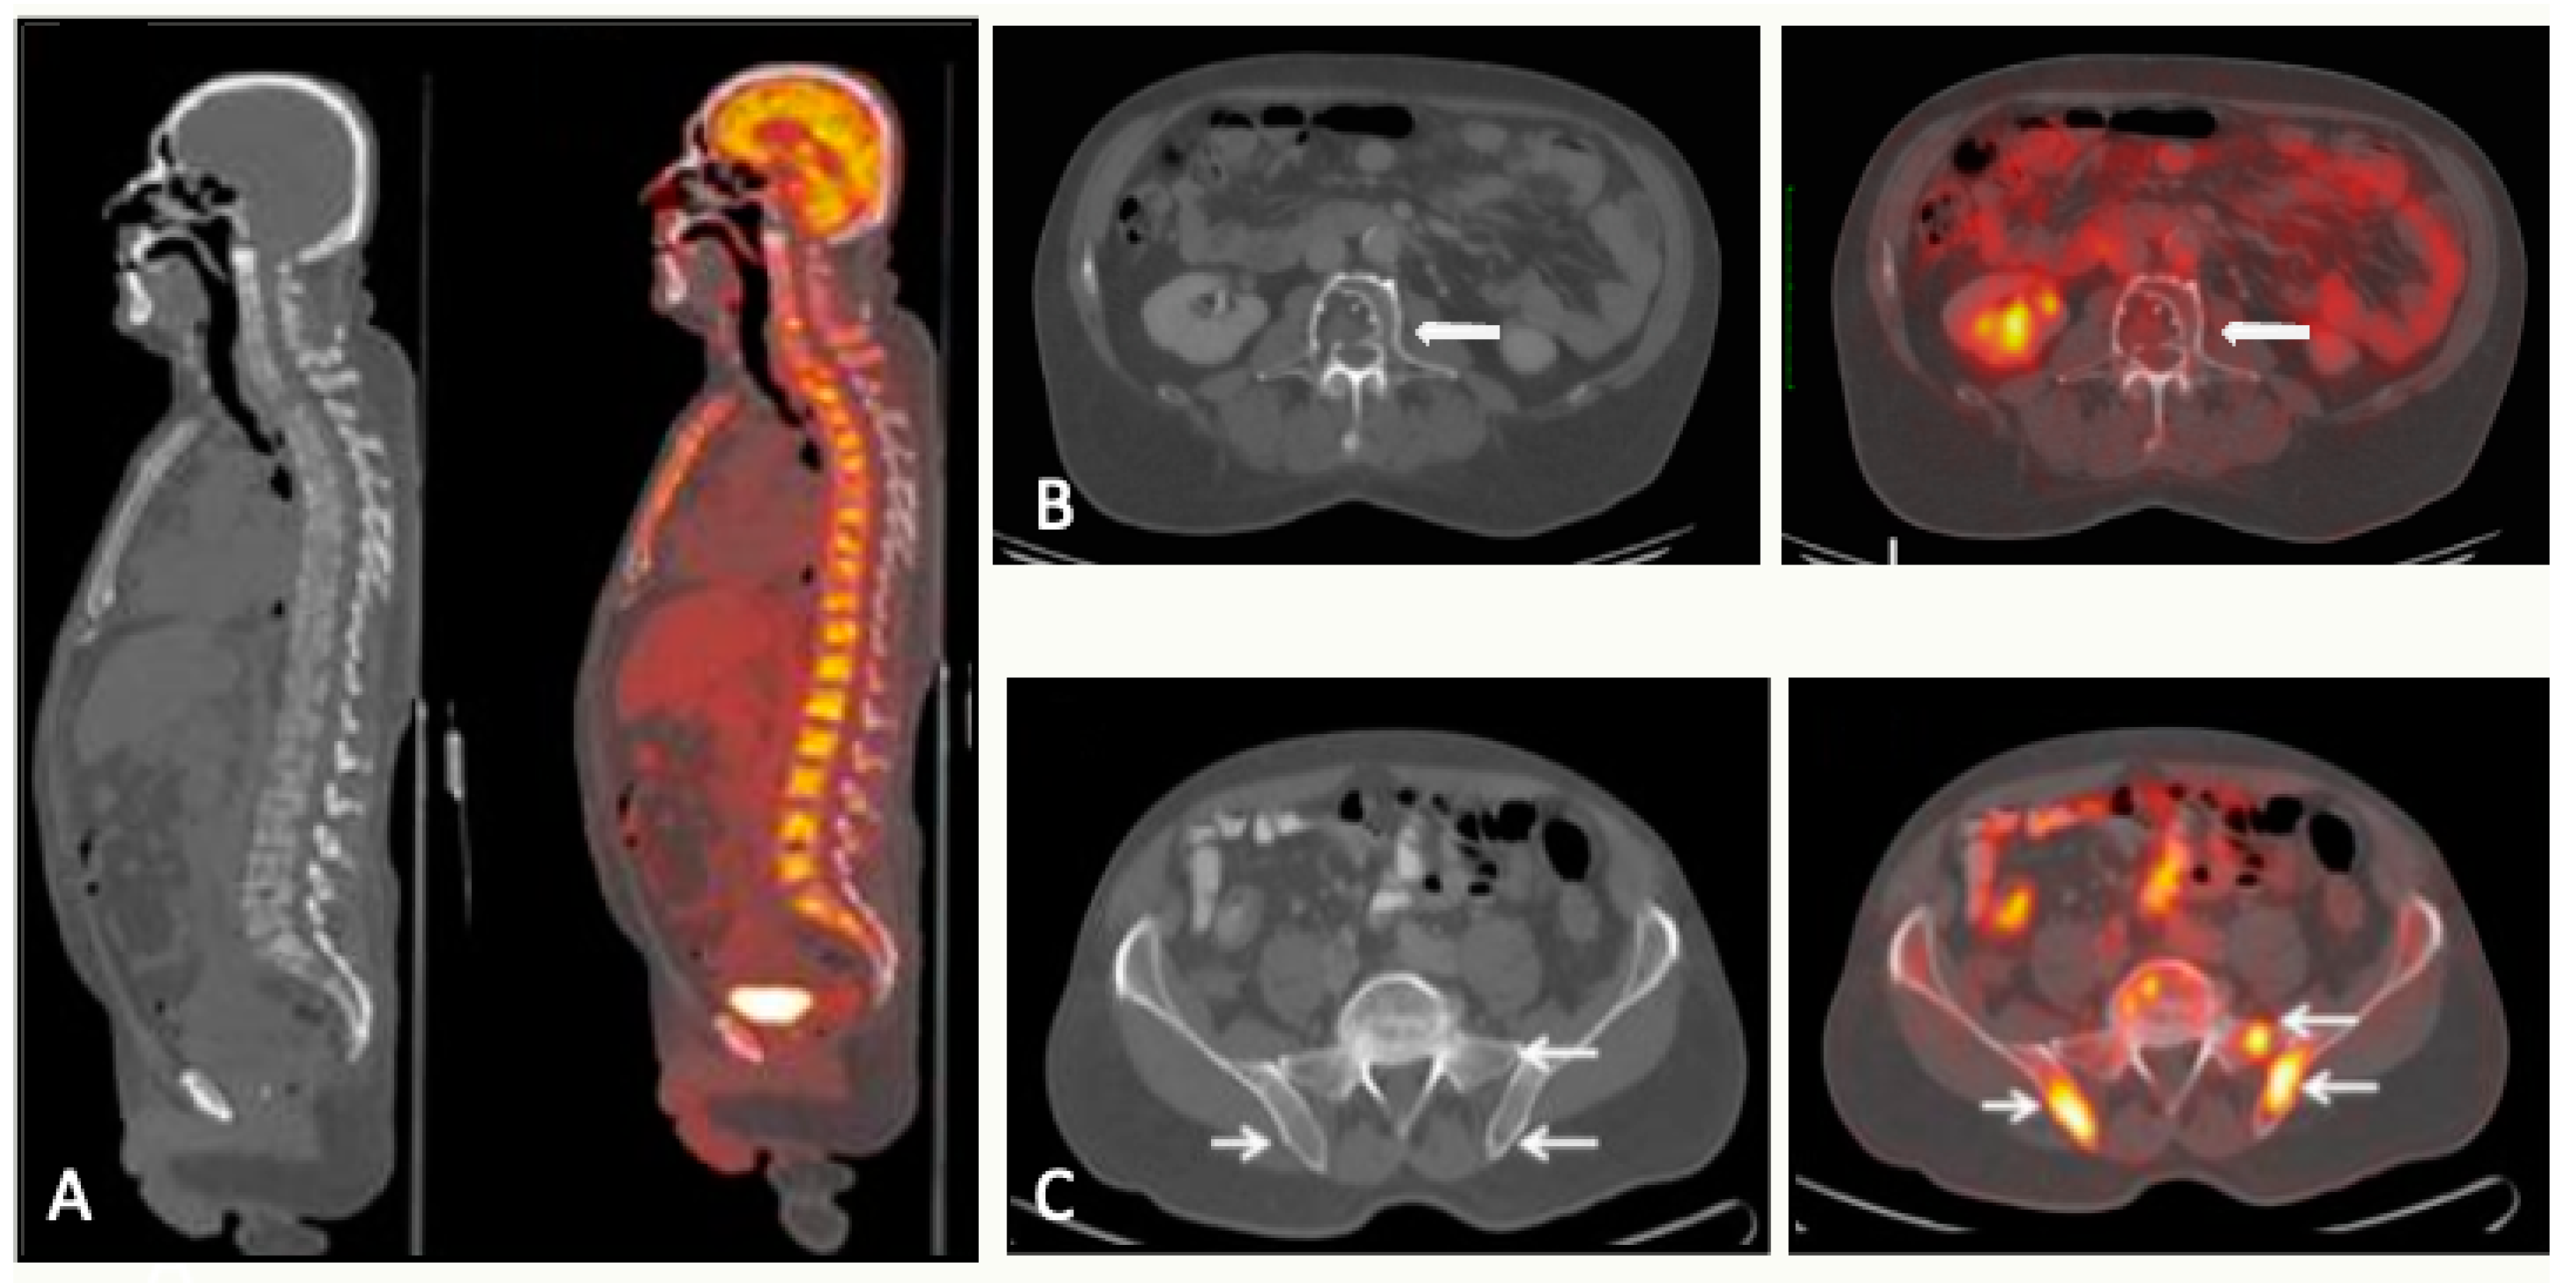

5.1. PET/CT

5.1.1. Technique and Image Analysis